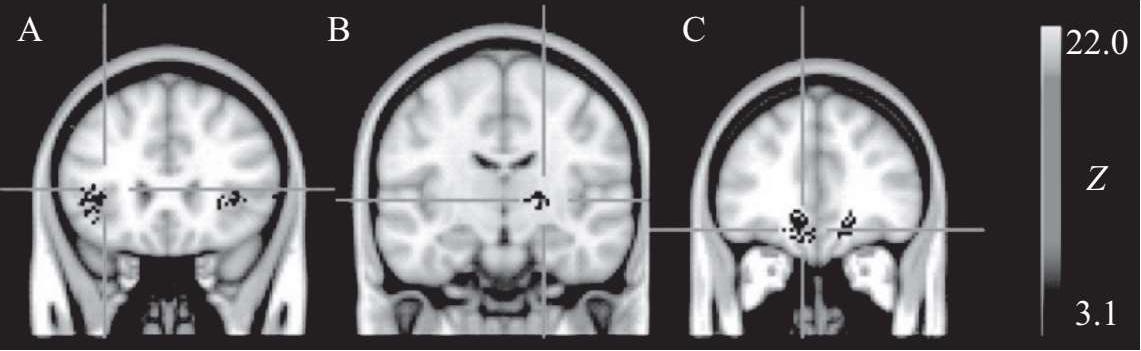

值得注意的是,正确选择奖励的类别至关重要,如使用物质奖励存在一定风险。想象一下,每次人们用物质奖励激励孩子时,都可能传递一个错误的信息:一切都可以用物质来衡量。频繁地用小零食和糖果作为奖励可能是不明智的,因为甜食和高脂食物对大脑来说非常愉悦。随着孩子的成长,每当他渴望满足时,大脑可能会发出需要糖果或其他适口性食物的信号,这可能导致食物成瘾,甚至造成肥胖的发生。因此,人们更应该以社会性奖励的形式激励孩子们,通过感谢、祝贺和赋予一些特权来激励他们的劳动。如果人们将与孩子一起玩游戏或进行体育活动作为奖励方式,孩子可能会意识到合作是快乐而且重要的,这是一种极其重要的品质。此外,需要注意的是,奖励必须在孩子完成有价值的事情之后及时给予,适当的时间非常关键。一般情况下,行为与奖励之间的时间越短,奖励越有效。举例来说,如果人们的目标是让孩子连续一周每天都把自己的衣服放在洗衣篮里,对一个孩子来说可能并不容易。如果人们在洗衣篮上画上一个笑脸,并每天更新日期,就可以给孩子一种满足感,他自然就获得了奖励并强化了这种行为。在后天学习、训练以及经验等因素的影响下,大脑皮层会发生结构变化和功能重塑。在儿童青少年时期,个体认知能力迅速提高,中枢神经系统的可塑性也最强。功能性磁共振成像的结果表明,练习和训练可以促使大脑活动模式发生变化。

高强度运动可增加大脑奖励相关区域对低热量食物图像的神经反应(Crabtree D R,2014)

在肥胖防治领域,关键的研究方向之一是探索运动如何通过增加能量消耗来帮助减轻体重。然而,探讨运动是否能通过激励机制调节饮食行为和能量摄入的研究相对较少。近期的发现揭示了一些有趣的现象:例如,急性运动后,肥胖青少年的能量摄入和对食物相关信息的神经反应都有所下降,这一现象在非肥胖受试者中则未观察到。这意味着,尽管肥胖者运动后的总能量摄入未显著降低,但由于运动导致的能量消耗,能量平衡可能发生了变化。运动不仅可能增加饱腹感,还可能抑制由于享乐驱动的饮食行为。此外,运动锻炼对肥胖青少年体内与食欲相关的激素水平,如胰岛素、瘦素和生长激素释放肽等,都有显著影响。这些激素可能通过直接或间接作用于大脑的奖励系统(特别是VTA-NAc-DA神经元)来调节饮食行为和进食后的奖励感受。